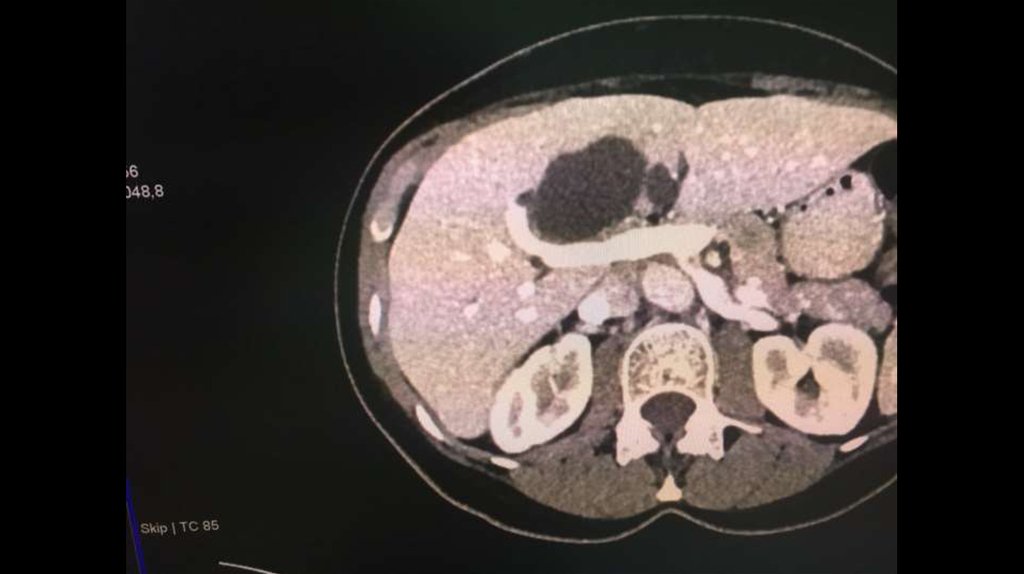

По направлению из ЦГБ в ККБ №1 поступил пациент М., 48 лет, с диагнозом «Эхинококкоз

печени»

Пациенту в плановом порядке выполнено КТ ОБП. По результатам исследования выявлена

эхинококковая киста IV-V сегментов.